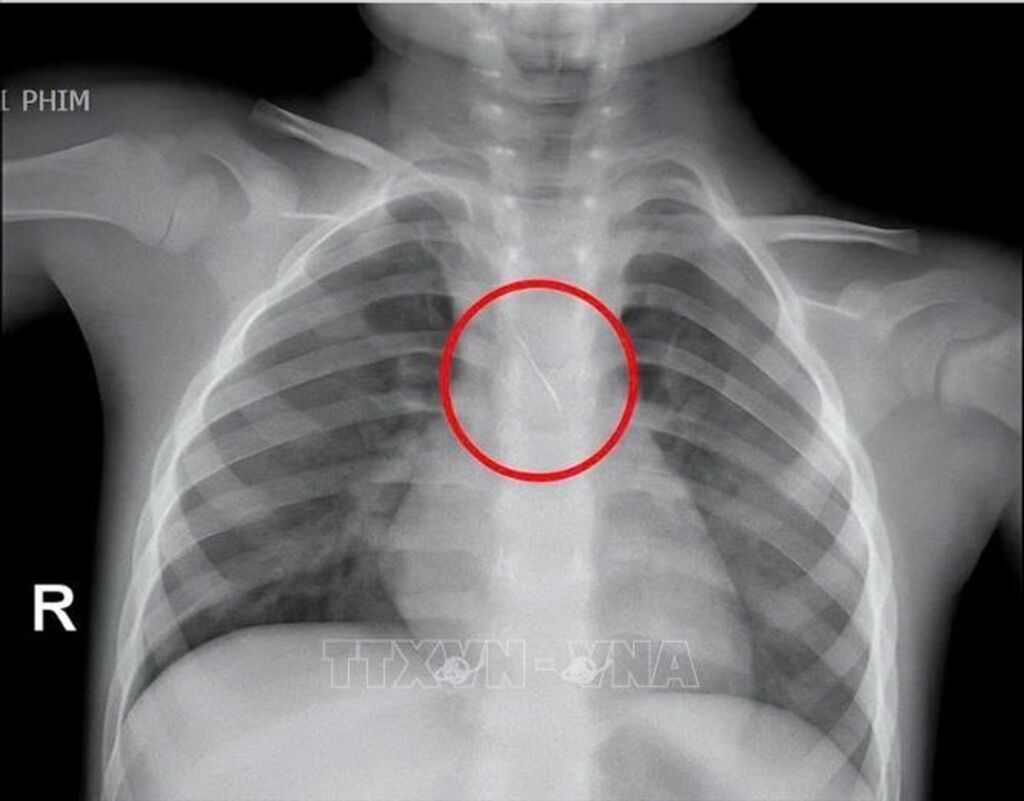

Hình ảnh chiếc kim chọc tuỷ rơi vào trong đường thở của bé trai 3 tuổi.

Trước đó, bệnh viện tiếp nhận bé N.Q.T.Đ (3 tuổi), trú tại xã Cửa Việt, Quảng Trị trong tình trạng ho nhiều, ho sặc. Kết quả chụp phim cho thấy, một dị vật kim loại dài khoảng 22mm nằm ở góc carina (vị trí chia đôi khí quản) đe dọa gây tắc nghẽn đường thở của trẻ.

Ngay lập tức, các bác sỹ đã hội chẩn liên khoa và quyết định nội soi phế quản cấp cứu. Dị vật được phát hiện có một đầu nhọn cắm vào 1/3 dưới khí quản, đầu còn lại nằm trong phế quản gốc trái, được xác định rất nguy hiểm. Sau 15 phút thao tác khẩn trương, dị vật được kíp mổ lấy ra an toàn. Bé trai cải thiện triệu chứng ngay sau can thiệp và xuất viện sau 48 giờ theo dõi.